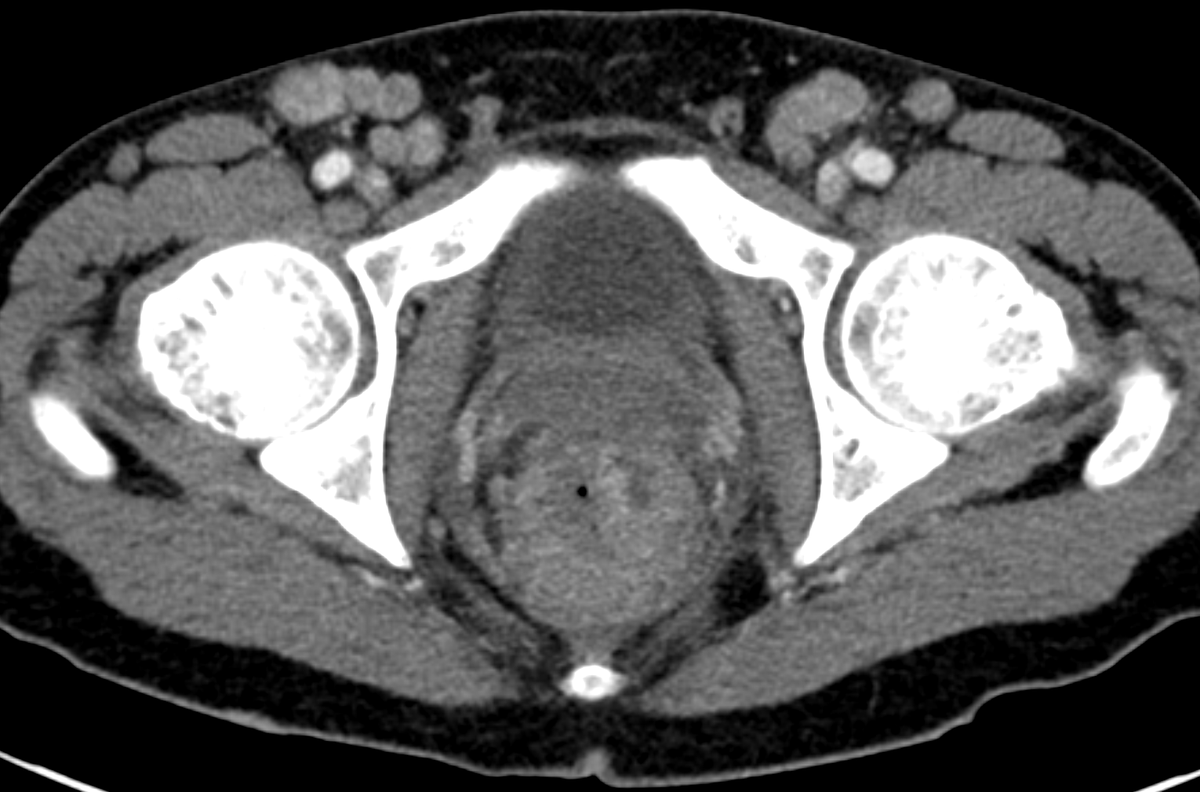

If you're having trouble choosing between an extracellular or hepatobiliary contrast agent for liver MRI, why not both? Read about the indications, protocol, and utility of dual-contrast liver MRI, now available in @RadioGraphics at pubs.rsna.org/doi/10.1148/rg…